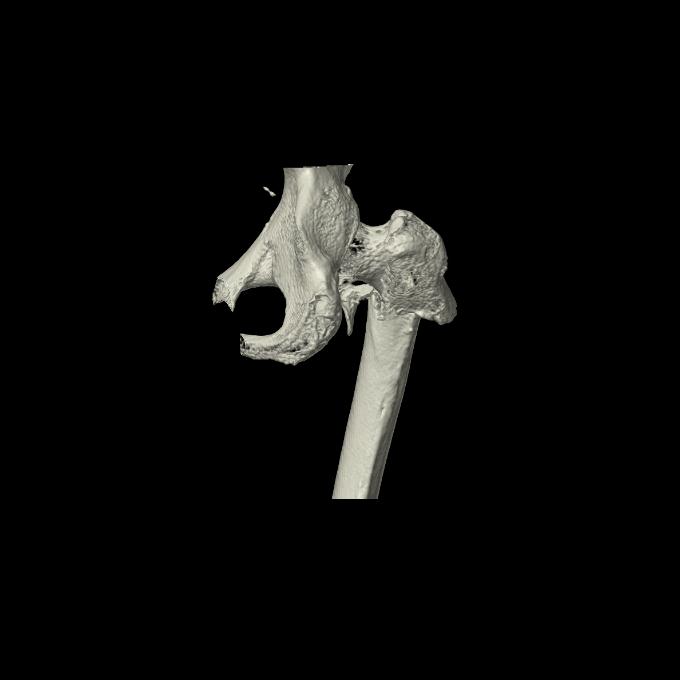

46666 1/28 両股正面+軸と 1/26 右手関節 2R 76歳女性 右転子部骨折

37 1/18 両股正面+軸 1/22 2R 86歳女性 右転子下